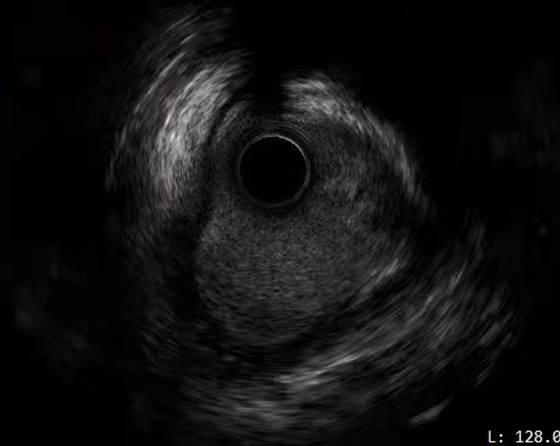

手术过程中,由周玉杰教授团队在操作端操作控制,ETcath血管介入机器人在手术室精确地实施了对患者的PCI手术。冠状动脉造影显示LAD近段重度狭窄,同时通过介入机器人成功推送导丝到达前降支远段 然后使用IVUS超声导管检查,证实血管狭窄程度较重。

术后超声